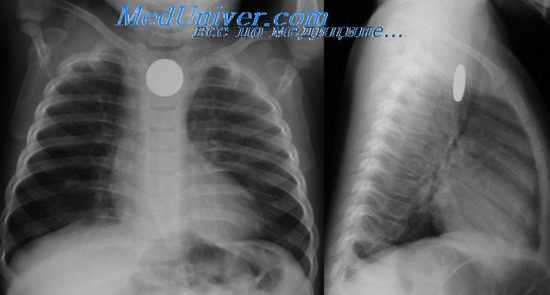

• Изменения на рентгенограмме: назогастральный зонд упирается в слепо заканчивающийся проксимальный сегмент пищевода. При атрезии пищевода без трахеопищеводного свища (тип 2) на рентгенограмме отсутствует газовый пузырь желудка. В некоторых случаях для выявления анатомических деталей требуется введение рентено-контрастного вещества.

При втором распространенном варианте имеются 2 изолированных отрезка пищевода — проксимальный и дистальный, — не сообщающихся с дыхательными путями. Как и при атрезии пищевода с трахеопищеводным свищом его дистального отрезка, наблюдается обильное выделение слизистого секрета изо рта, срыгиваиия, приступы асфиксии, но живот запавший и газ в желудочно-кишечном тракте не обнаруживается ни при объективном осмотре, ни при рентгенографии.

Подозрение на атрезию пищевода возникает при невозможности провести назогастральный зонд. Отсутствие газа в желудочно-кишечном тракте на рентгенограмме подтверждает диагноз атрезии пищевода без трахеопищеводного свища. Контрастное рентгенологическое исследование в большинстве случаев помогает оцепить длину проксимального отрезка пищевода. У большинства детей она невелика и расстояние между слепыми концами отрезков значительно (атрезия с большим диастазом).

На обзорной рентгенограмме органов грудной клетки и брюшной полости при атрезии пищевода определяется его слепой проксимальный отрезок, наличие воздуха в желудке и кишечнике при дистальном трахеопищеводном свище, и отсутствие их газонаполнения при изолированной форме заболевания. Использование в диагностике атрезии пищевода бариевой взвеси крайне нежелательно из-за высокого риска респираторных осложнений и летального исхода.